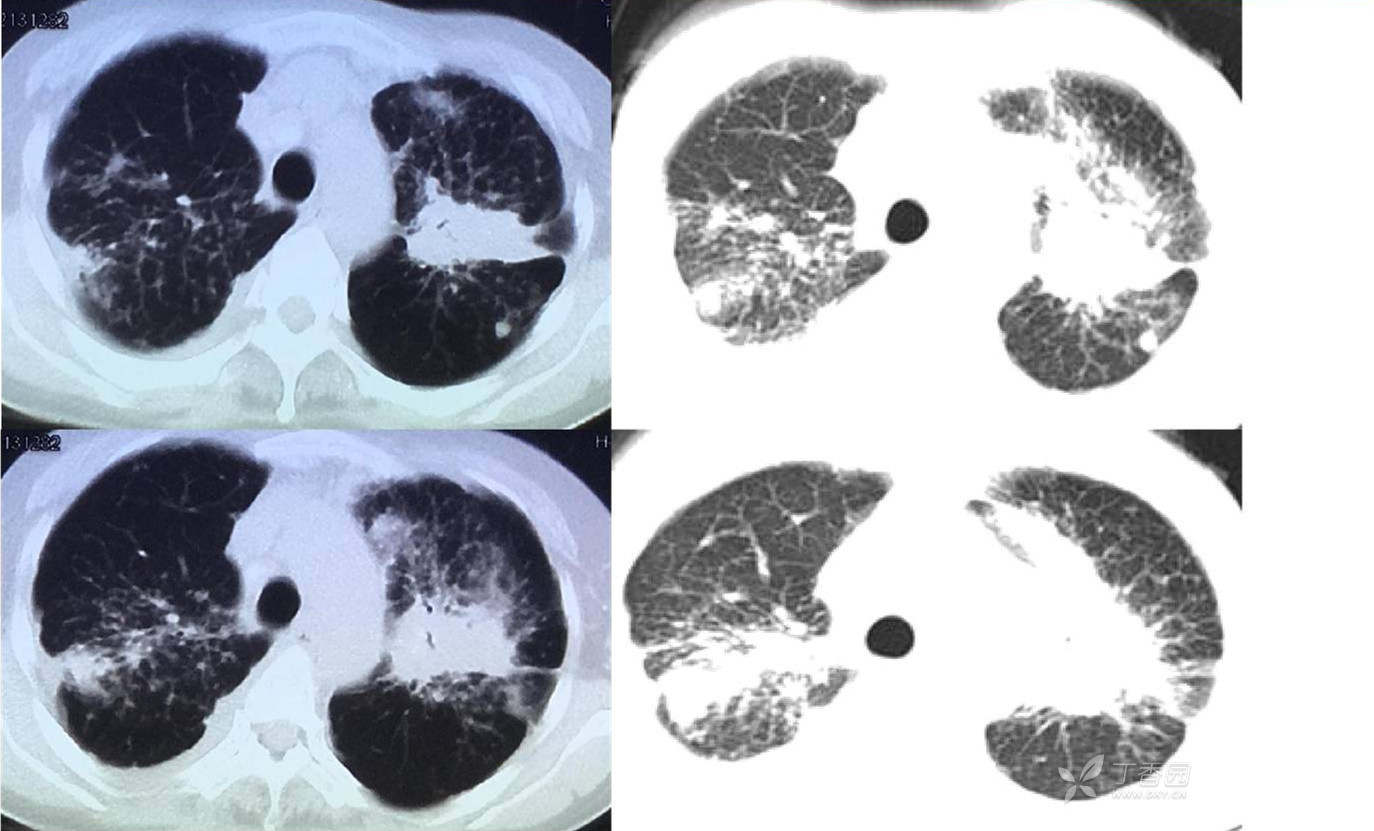

辅助检查:CT

第一次胸部CT

临床诊断:双肺弥漫性病变